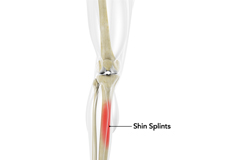

Shin Splints

Shin splints are pain and inflammation of the tendons, muscles and bone tissue along the tibia or shinbone (lower leg). It occurs because of vigorous physical activities such as exercise or sports. The condition is also referred to as medial tibial stress syndrome (MTSS).